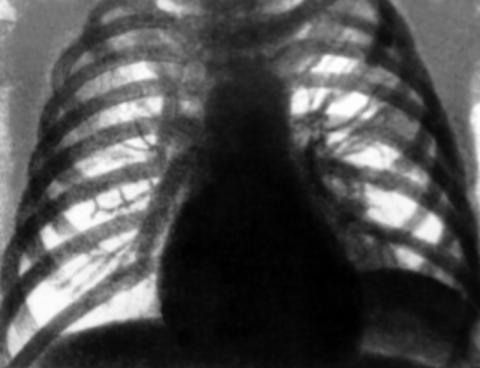

При осмотре отмечаются некоторое расширение и выбухание межреберных промежутков. Нарастающий объем жидкости оттесняет легкое кпереди и вверх, вследствие чего слой жидкости сзади становится более толстым, что при перкуссии очерчивает верхний край жидкости в виде линии Дамуазо, верхняя точка которой приходится на лопаточную линию. Над выпотом определяется тупой перкуторный звук. Важным клиническим симптомом наличия свободной жидкости является неподвижность нижнего легочного края. При значительных выпотах границы относительной сердечной тупости смещаются в здоровую сторону. Границу относительной сердечной тупости на стороне выпота можно установить с помощью метода аускультативной перкуссии. При аускультации над выпотом определяется ослабление или исчезновение дыхательных шумов, голосового дрожания и бронхофонии, однако при плевральных сращениях в зоне выпота эти симптомы могут отсутствовать. Непосредственно над выпотом может выслушиваться бронхиальное дыхание.

Важным признаком ПВ является смещение органов средостения. При парапневмонических плевритах средостение смещается в здоровую сторону. При выпоте, который сочетается с ателектазом или с пневмоциррозом, - в сторону поражения. Смещение органов средостения в сторону поражения при вторичном опухолевом плеврите при раке легкого является неблагоприятным прогностическим признаком.